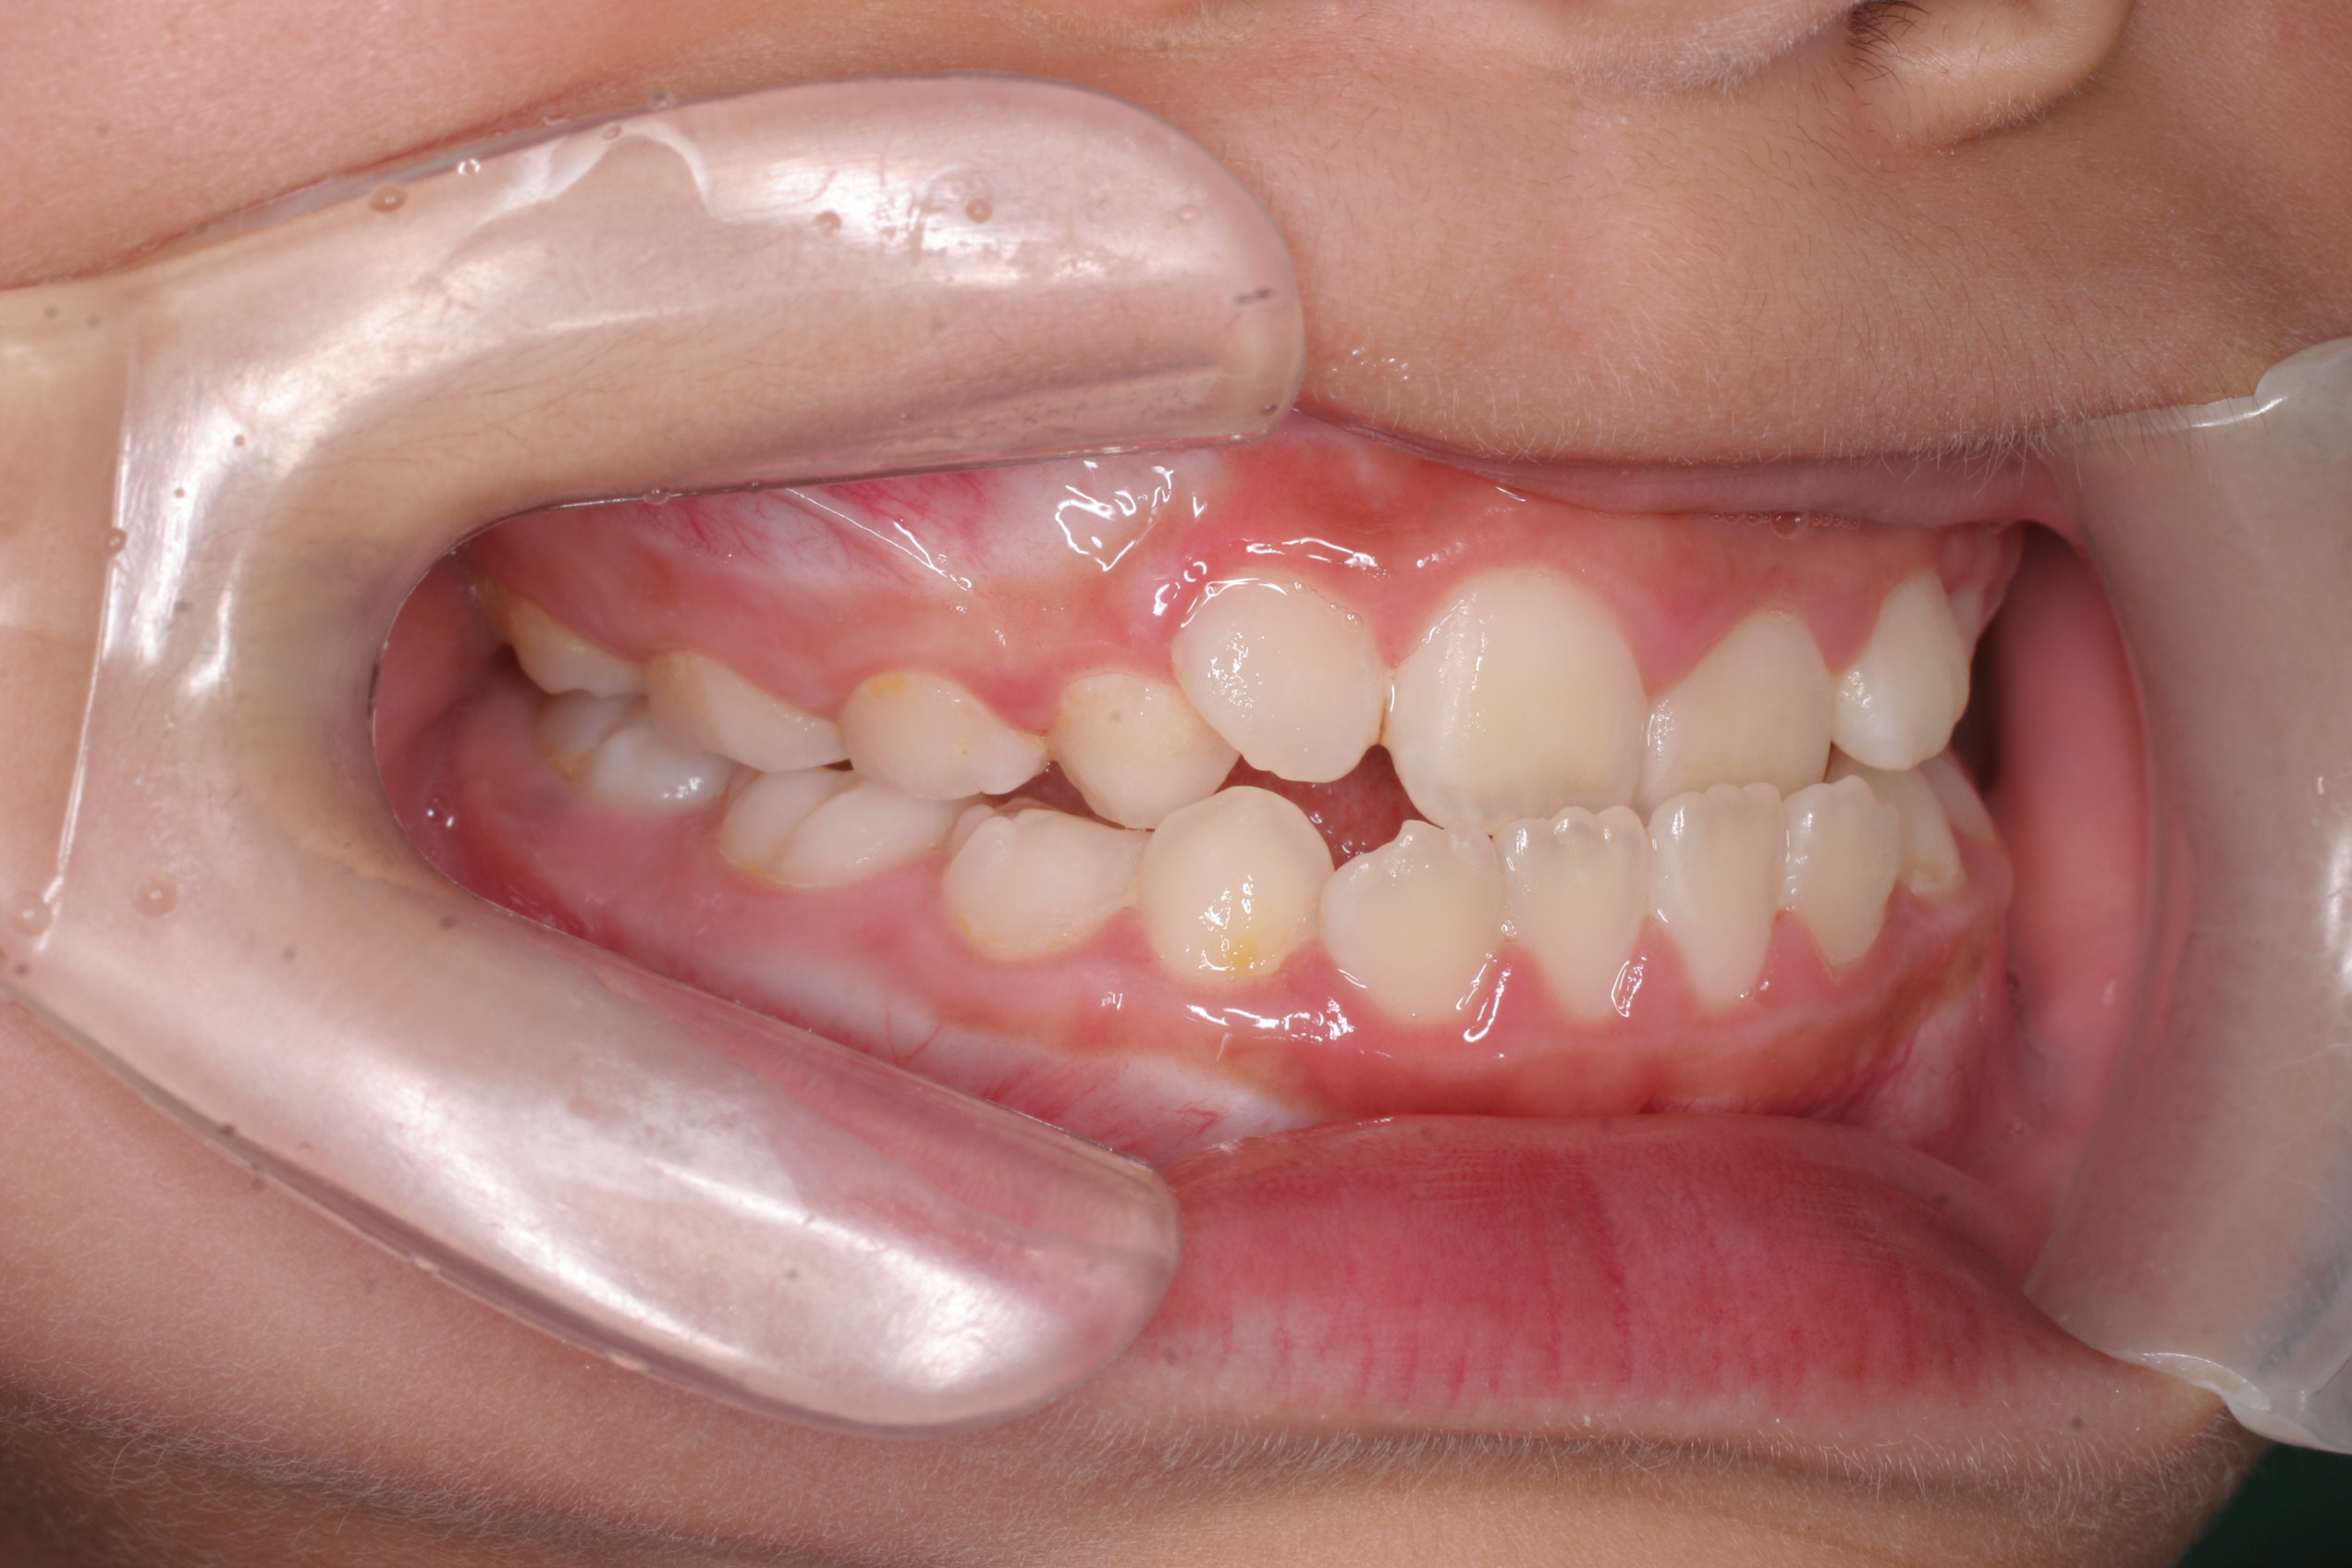

叢生

叢生(そうせい)とは、歯並びのガタガタのことです。一般的には乱杭歯(らんぐいば)、八重歯(やえば)と呼ばれることもあります。叢生は、あごの骨の大きさに対して歯が大きく、きれいに並ぶスペースが不足している場合に起こります。叢生の歯並びでは、歯が重なり合った場所を正しく歯磨きすることは難しく、虫歯や歯周病の原因になることがあります。

叢生は、歯を並べるスペースを確保し、マルチブラケット装置等で歯を移動させて治療を行ないます。歯を並べるスペースが大きく不足しているときは、抜歯が必要になることがあります。

混合歯列期のお子さまの場合は、あくまでも個人差がありますが、あごの成長を助ける装置を使うことによって永久歯萌出のためのスペースを確保できることがあります。それによって抜歯による矯正治療をさけることが可能になります。